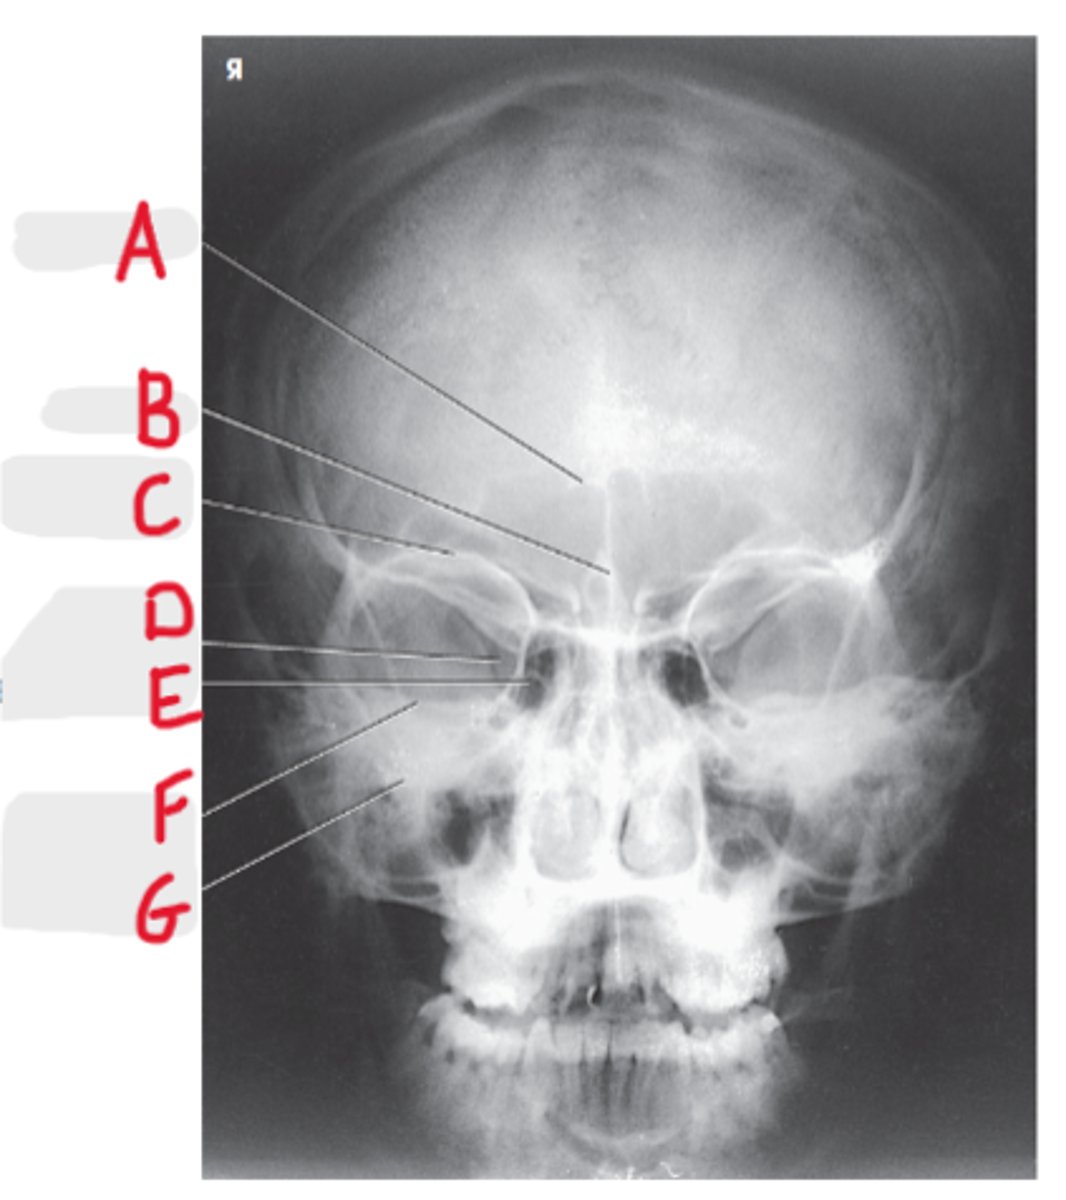

Parietoacanthial (Waters Method)

What projection is this?

CR to exit at acanthion

What is the CR for the Parietoacanthial (Waters Method)?

MML perpendicular to IR

What line should be perpendicular to the IR on a Parietoacanthial (Waters Method)?

Maxillary Sinuses

What sinuses are best demonstrated on the Parietoacanthial (Waters Method)?

37 degree angle from IR plane

What angle should the OML be at for a Parietoacanthial (Waters Method)?

Equidistant lateral border of skull and lateral borders of the orbits

How do we look for rotation/tilt for the PA Caldwell or Waters?

Pretrous ridges lie inferior to maxillary floor

Where do the petrous ridges (pyramids) lie on a Waters radiograph?

Maxillary sinus

A

Ethmoid air cells

B

Mandible

C

Sphenoid Sinus

D

Foramen spinosum

E

Mandibular condyle

F

Dens or odontoid process

G

Petrosa

H

Mastoid process

I

Occipital bone

J